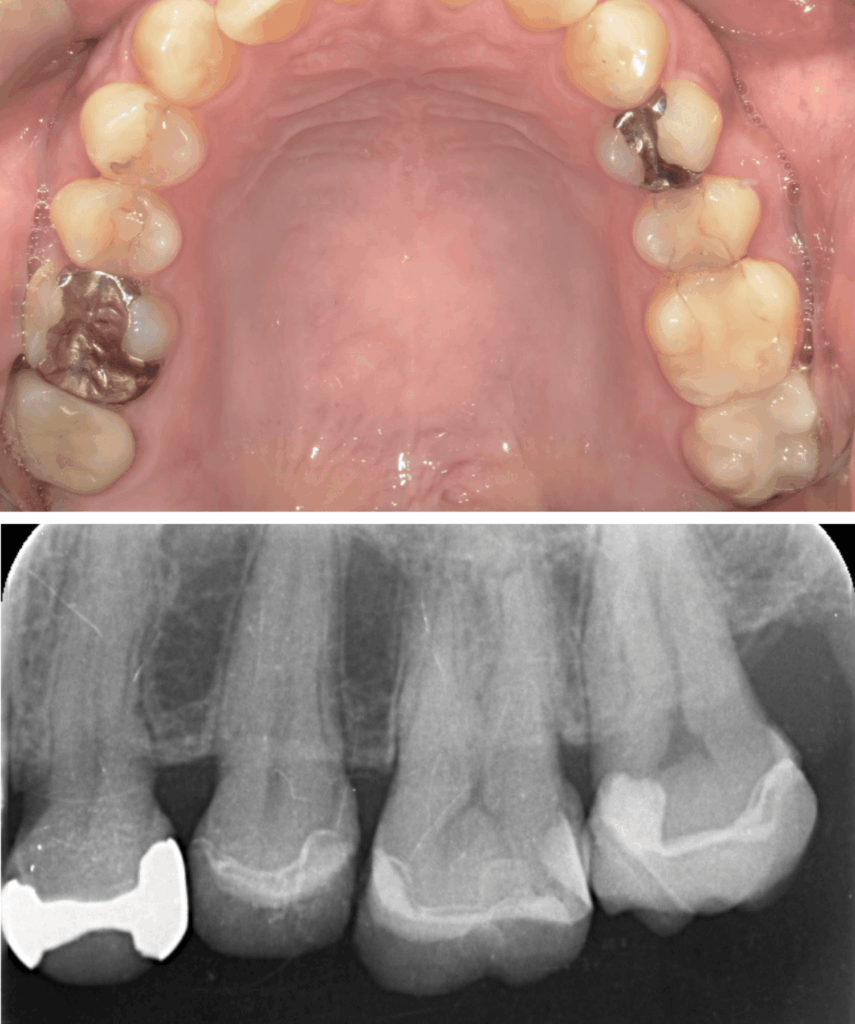

歯と歯の間のう蝕の為肉眼では分かりにくく、気づいた時には歯髄に近接し、保険治療では抜髄(神経を除くこと)になってしまうケースが多い。そのため処置前に、十分な精査と、患者さんが神経を残したいという希望の有無をしっかり相談・説明することが重要と考えています。

歯髄を温存し症状が出ないか1か月経過観察のためCRにて修復

お口の写真で青の部分があるのは、視覚的に保護剤と自分の歯がわかりやすいように区別するため一次的に青のCRを用いた

| 診断 | ①右上7根尖性歯周炎 ②重度う蝕 ③左上7歯髄に近接するステージ3のう蝕 |

| 処置内容 (または主訴) | ①マイクロスコープによる根管治療 ②マイクロスコープによるう蝕除去およびセラミック修復 ③MTAを用いたマイクロスコープによる歯髄温存療法からセレック修復 |